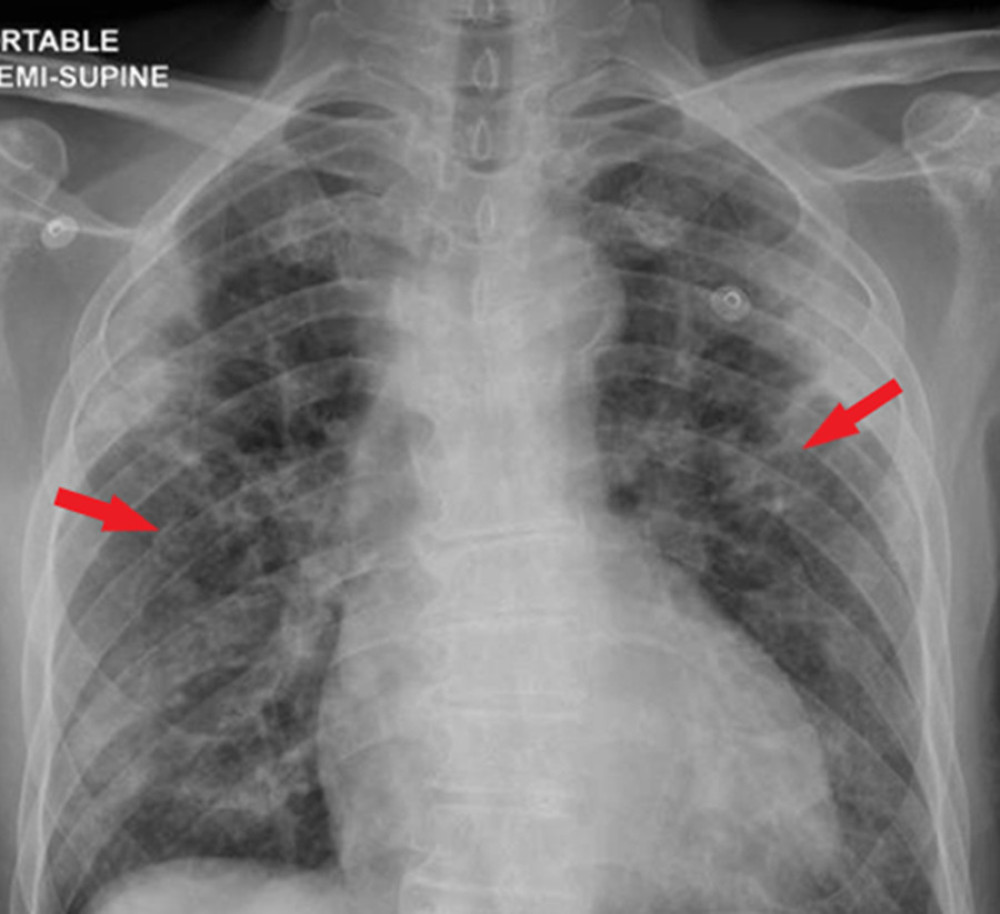

Bilateral infiltrates in a healthcare worker during the COVID19 Chest X Ray Infiltrates Covid Chest radiography (cxr) is a widely available baseline radiological modality in evaluating symptomatic patients with suspected or. However, chest radiography of people who are seriously ill with. Chest X Ray Infiltrates Covid.

Chest radiograph showing diffuse, patchy bilateral inte Openi Chest X Ray Infiltrates Covid However, chest radiography of people who are seriously ill with. Chest radiography (cxr) is a widely available baseline radiological modality in evaluating symptomatic patients with suspected or. Chest X Ray Infiltrates Covid.